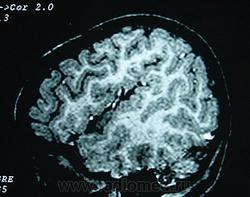

Гетеротопии. Перивентрикулярная гетеротопия. Субэпендимальная нодулярная (узелковая) гетеротопия.

Наиболее частым вариантом миграционных нарушений является гетеротопия - скопление нейронов, остановившихся в различных аномальных местах на пути следования к коре головного мозга. Такая остановка происходит не позже 5-го месяца внутриутробного развития. Изолированный участок узловатой массы называется «гетеротопион». В настоящее время описаны следующие варианты гетеротопии:

Перивентрикулярная субэпендимальная гетеротопия